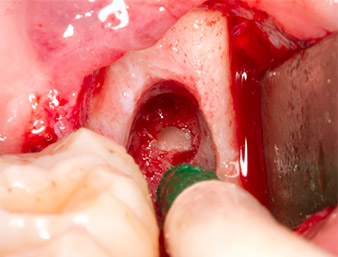

Nach Leitungs- und Lokalanästhesie wurde das Operationsfeld für einen bukkal-retromolaren Zugang weichgewebig eröffnet und dargestellt (Abb. 3).

sulkuläre Schnitt

Abb. 3: Der sulkuläre Schnitt beginnt Mitte des Zahnes 36, mit distaler Verlängerung am aufsteigenden Ast.

Granulationsgewebe

Abb. 4: Zwei Langenbeck-Haken und ein Raspatorium nach Prichard stellen das OP-Feld dar. Granulationsgewebe der unvollständig abgeheilten ersten Osteotomie ist zu erkennen.